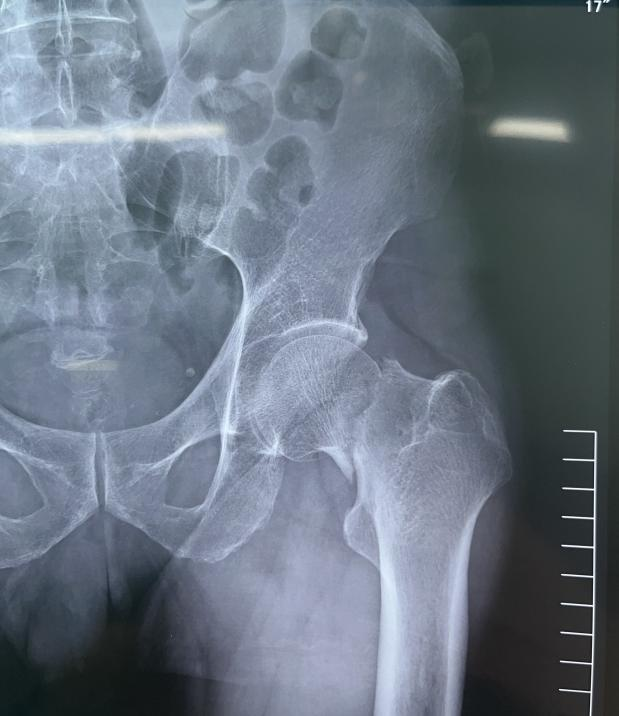

股骨颈骨折术前X片